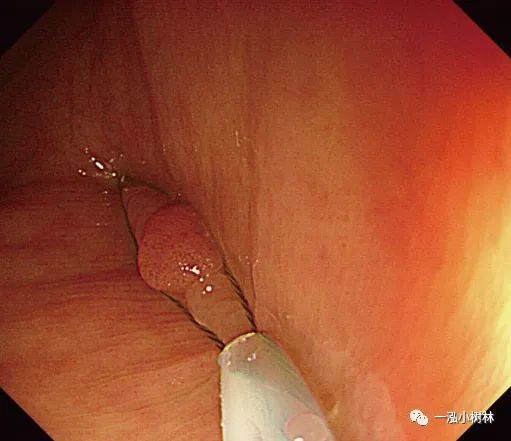

2.最近的一项随机研究表明,在内镜下对小息肉的治疗中,CSP技术优于冷钳息肉切除术,并且在完整性和操作时间方面均优于冷钳息肉切除术。

3.将息肉边缘正常黏膜包括在内,用圈套器夹住并机械横切。切取的速度要快,因为慢的横切会造成黏膜下组织大量的损伤和随后不必要的出血。

4.下一个重要步骤是将息肉切除部位的标本通过结肠镜钳道吸入。切除息肉后,应将结肠镜头指向切除部位,随后吸引。

5.CSP技术可能导致息肉切除失败和黏膜出血。在最近的随机试验中,息肉的切除率是93.2%~96.0%。在不服用抗血小板药物或抗凝剂的患者中,大多数黏膜出血是自行停止的,没有明显出血的危险。

例5 小息肉冷圈套切除术

图片

图5a 横结肠处4mm大小0-IIa型腺瘤

图5b 在病灶上方圈套

图5c 圈套包括病灶周围1-2mm正常黏膜

图5d 对病变进行机械性横切

图5e 对病变进行机械性横切

图5f 息肉取出后出血

图5g 黏膜出血止血

图5h 可见息肉边缘正常黏膜的标本